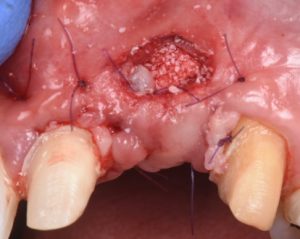

This video presents Part 2 of a staged pontic site development protocol, performed five months after the initial soft tissue augmentation. The objective of this second surgery is to further enhance soft tissue volume and achieve root coverage in preparation for a future fixed partial denture (FPD).

The procedure demonstrates the use of a horizontal vestibular incision with tunneling to mobilize the soft tissues and elevate the papillae. An autogenous connective tissue graft (CTG) harvested from the palate and maxillary tuberosity is utilized to augment tissue thickness. Additionally, a xenogenic bone graft is placed over the crestal area to serve as a space-maintaining scaffold and support vertical tissue stability.

- Use of xenograft as a space-maintaining adjunct for vertical support